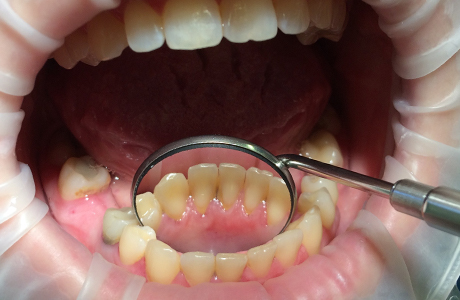

До и после лечения

В «Стоматологию Комфорта» обратилась пациентка с жалобой на твёрдые зубные отложения, которые не поддаются удалению в домашних условиях. В ходе личного осмотра врач стоматолог-терапевт Вахлюева Елена Сергеевна обнаружила зубной камень, затвердевший налёт и назначила пациенту профессиональную гигиену полости рта.

Процесс чистки включал в себя:

- безболезненное снятие твёрдых отложений с помощью ультразвука;

- удаление пигментации от чая, кофе, курения и других красящих продуктов;

- полировку с целью предотвращения новых отложений;

- фторирование зубов с использованием специальных паст для укрепления эмали.